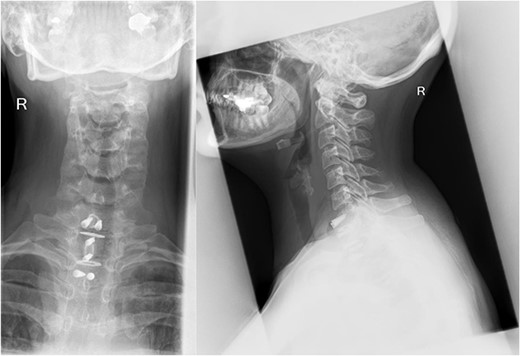

There were no surgical complications intraoperatively or postoperatively. A 3-day postoperative X-ray determined there was no mispositioning of the VBR and instrumentation (Fig. 3). There were no inpatient medical complications and pain was managed appropriately. Patient was discharged from hospital shortly after the operation and recovery. As outpatient, she did not complain of pain or wasn’t immobilized outside of the hospital. A 15-month follow-up MRI and 30-month follow up Positron emission tomography–computed tomography (PET-CT) maintained to show that the patient was tumour free (Figs 4 and 5). Lastly, upon assessment in clinic over 30 months, the patient was fully mobile and self-reported to be pain free, living independently and comfortably. There were no hardware related issues and there wasn’t any development of infection.

A 3-day postoperative X-ray of VBR and instrumentation in coronal (Right) and sagittal (Left) view.